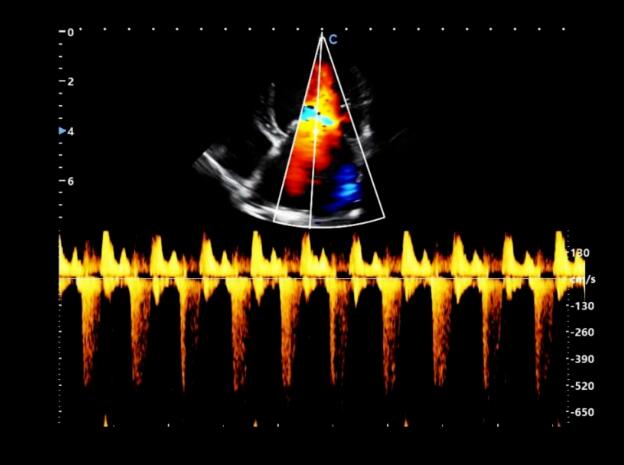

Finally, continuous wave doppler was used to measure the regurgitation velocity at the mitral valve in the left apical four chamber view.

The examination results of the dog's heart showed that, MMVD caused mitral regurgitation, and left ventricular systolic retrograde mottled blood flow.

Doppler echocardiography is very intuitive for diagnosing mitral regurgitation. The size and depth of its reflux also indicate the severity of the reflux.